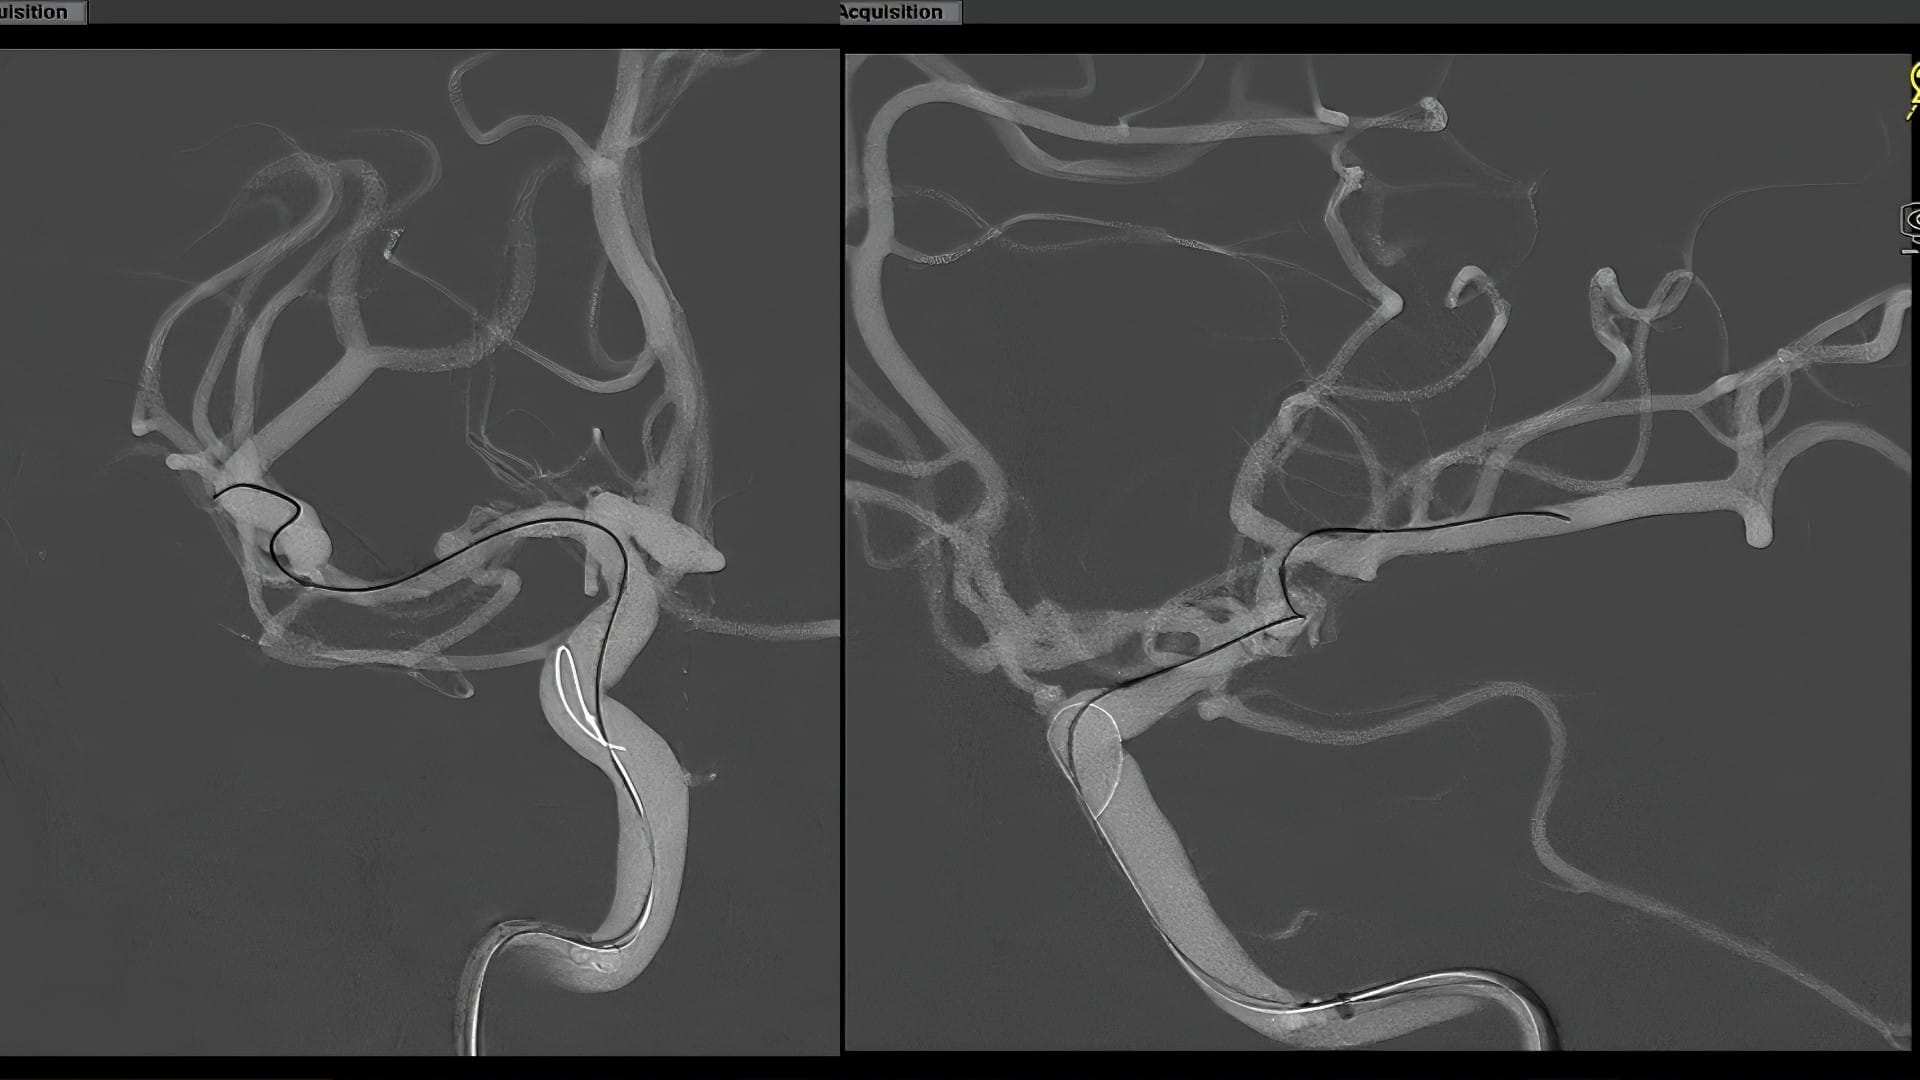

Ángulos de trabajo y colocación precisa

Se planificaron cuidadosamente los ángulos de trabajo para visualizar claramente tanto el cuello del aneurisma como el extremo distal del stent durante su despliegue.

Técnica de microcatéter y embolización con coils

Se utilizaron dos microcatéteres Headway 17. Uno de ellos fue avanzado distalmente para preparar el despliegue del stent, y el otro se posicionó estratégicamente para la embolización.

Técnica semi-jailed y compactación de coils

Durante el coiling, se utilizó una técnica semi-jailed, que permitió una compactación eficaz de la masa de coils hacia el aspecto lateral del aneurisma, preservando el origen de la arteria lenticuloestriada.

Resultado final: oclusión completa y preservación arterial

El angiograma postoperatorio confirmó la oclusión total del aneurisma sin comprometer ramas arteriales importantes. La masa de coils se organizó con forma de croissant, protegiendo la anatomía vascular adyacente.